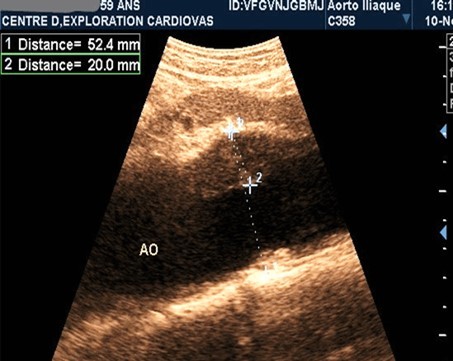

AAAs were fusiform in 23 patients (71.9%). The saccular aneurysm was present in 9 patients (28.1%). Figure 1 and (Figure 2).

Figure 1.Partially thrombosed 5.2cm fusiform suprarenal AAA with extension to the superior mesenteric artery in a 59-year-old subject (CEC 'Saint-Esprit' of the AMP-MCV).

Figure 2.Partially thrombosed 5.2cm fusiform suprarenal AAA with extension to the superior mesenteric artery in a 59-year-old subject (CEC 'Saint-Esprit' of the AMP-MCV).